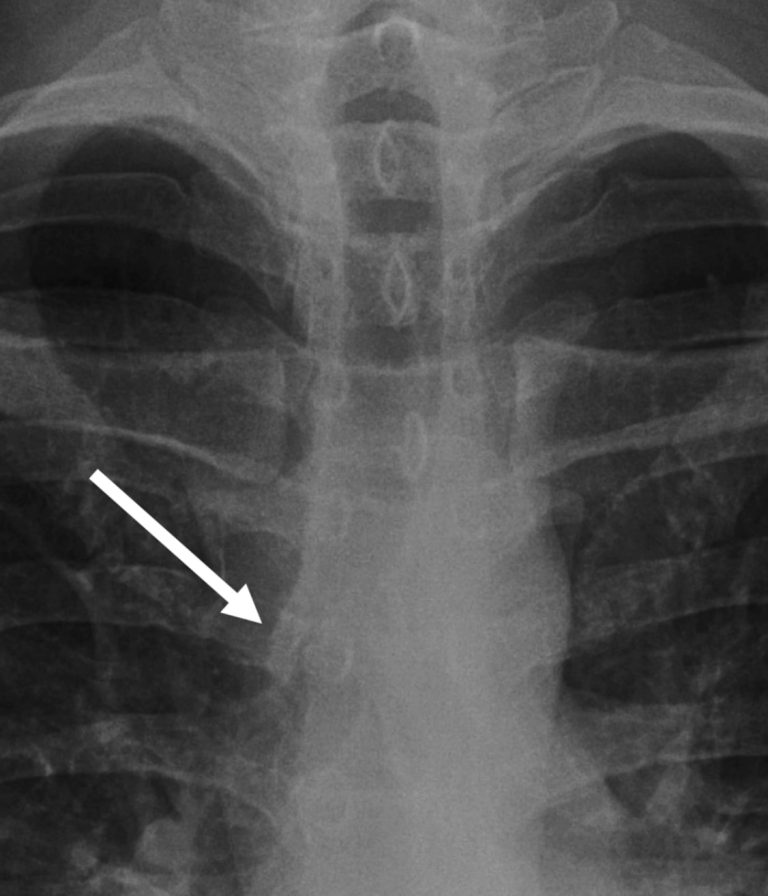

Assessing lung apices

Now let’s move onto the lungs. The first thing I do is to zoom up onto the lung apices as there are important things to exclude here.

The three things I look for are:

- Pancoast tumour

- Rib abnormalities

- Apical pneumothorax

A Pancoast tumour may be subtle, showing only asymmetry overlying the ribs, clavicles or in between them. If you’re not sure inverting the film and checking previous films help. I have called subtle opacities here and in retrospect this could have saved lives by calling an early lung cancer before it metastasised.

Next look at the bones. The bones all overlie each other at the apices so it is a good idea to try and piece it all apart. Identify the T1 and C7 transverse processes: the T1 transverse process will point upwards and the C7 one will point downwards. This helps you find your first rib arising at the level of T1 – trace this and the second rib looking for erosion (a destroyed rib could be a sign of a Pancoast tumour). Also look for a cervical rib arising from the C7 vertebra which could help explain symptoms of tingling or weakness in the upper limb.

Look at the spinous processes and ensure the interspinous distance is relatively similar: more than 1.5 times difference can be significant

Pneumothorax assessment

Let’s go into pneumothorax assessment in a bit more detail.

I do not consider a chest X‑ray fully reviewed until I have zoomed right in on both apices and that’s mainly because a pneumothorax can be very subtle unless you magnify the film. A pneumothorax represents gas within the pleural space – remember the pleura has two layers the visceral (inner) and parietal pleura (outer).

Pneumothorax represents gas within the pleural space, between the inner visceral and outer parietal pleura.

When a patient is upright, intrapleural gas will rise to the top, which is why pneumothoraces are usually detected here.

The two cardinal signs to look for are, firstly, a lucent black area of lung without visible vascular markings and, secondly, a thin white pleural line representing the visceral pleura separating from the parietal pleura. Compare side to side: if one apex lacks markings where the other has them, this should ring alarm bells. Bullae from emphysema can mimic a lucent pneumothorax, but these tend to be round and do not display a sharp pleural line paralleling the chest wall.

Here in this case we have the two cardinal signs of pneumothorax: one, a white pleural line (yellow arrow) and two lucency without lung markings outside of this.

In supine ITU patients, pneumothoraces may not rise to the apex and instead present as the ‘deep sulcus sign’ with an abnormally lucent and deepened costophrenic angle.